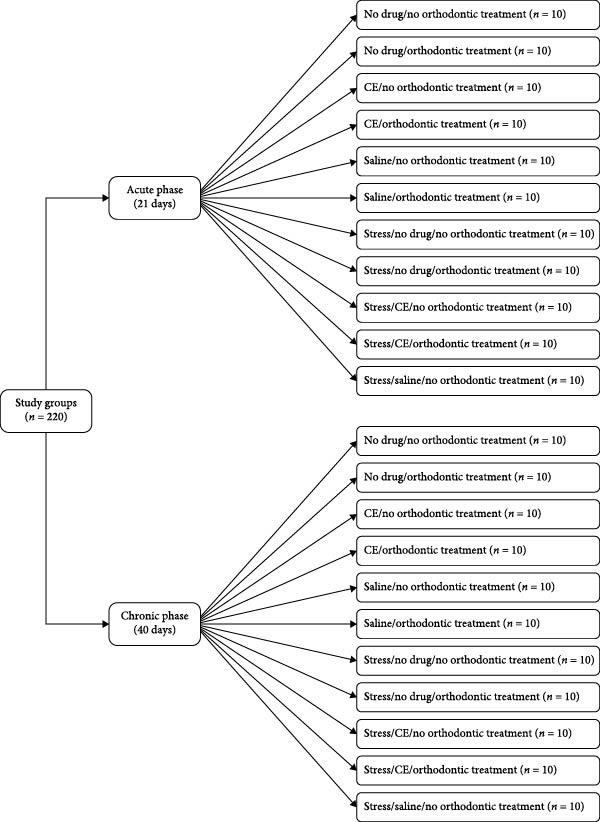

In this animal experimental study, 220 male Wistar rats were randomly assigned to 22 subgroups (n = 10) in two main groups of acute and chronic stress. The rats in the acute group were evaluated over a 21‐day period in the following 11 subgroups (1) no orthodontic treatment/no medication (2), orthodontic treatment/no medication (3), no orthodontic treatment/intraperitoneal CE injection (4), orthodontic treatment/CE injection (5), no orthodontic treatment/saline injection (6), orthodontic treatment/saline injection (7), no orthodontic treatment/no medication under stressful conditions (8), orthodontic treatment/no medication under stressful conditions (9), no orthodontic treatment/CE injection under stressful conditions (10), orthodontic treatment/CE injection under stressful conditions (11), no orthodontic treatment/saline injection under stressful conditions. The rats in the chronic group were studied over a 40‐day period in the following 11 subgroups with the same subgroups of the acute group. All rats were then sacrificed, their maxilla was resected, and OTM, the mean number of blood vessels, osteoclasts, and Howship’s lacunae, bone volume/total volume (BV/TV) ratio, and bone mineral density (BMD) were assessed.

The rats were randomly assigned to 22 subgroups (n = 10) in two main groups of acute and chronic stress. The rats in the acute stress group were evaluated over a 21‐day period in the following subgroups:

- The rats in this subgroup were subjected to stressful conditions. They did not undergo orthodontic treatment but received 1 mL/kg body weight saline on a daily basis (Figure 1).